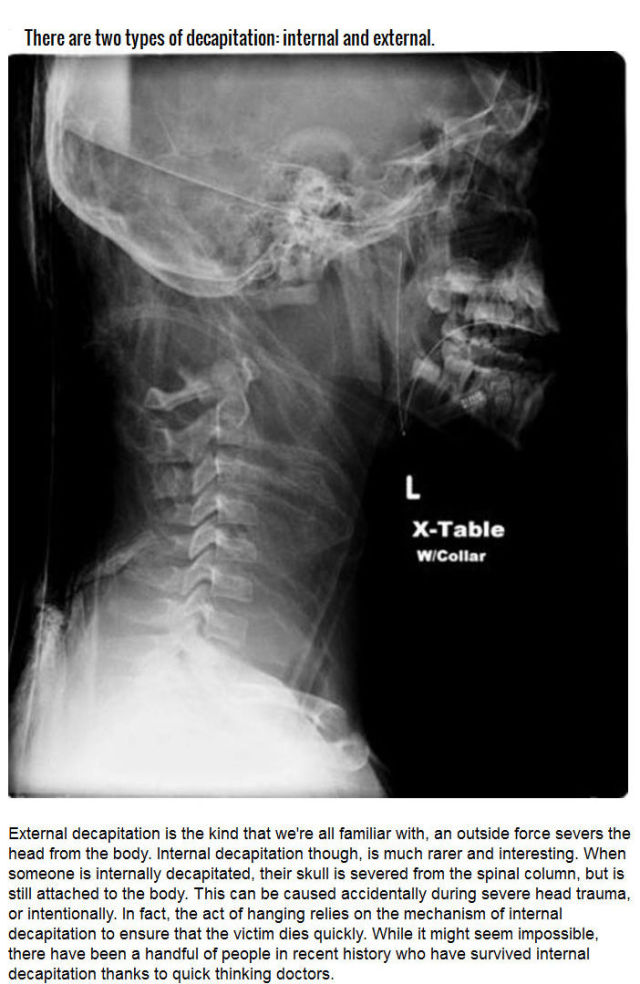

Beheading has been the most applied form of execution since the dawn of this, our current civilization. Second to it comes hanging, then burning, firing squads, electric chairs, gas chambers and now, lethal injections.